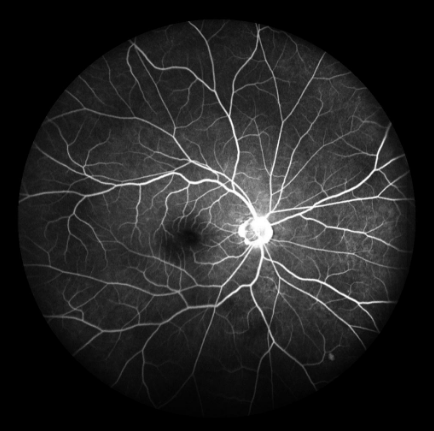

ICGA主要用于觀察脈絡(luò)膜的血管結(jié)構(gòu)和循環(huán)特點(diǎn),揭示脈絡(luò)膜循環(huán)的細(xì)節(jié),是目前PCV診斷的“金標(biāo)淮“。且由于吲哚青綠染料具有與熒光素鈉不同的特性,所以能更加直觀地了解脈絡(luò)膜血管循環(huán)狀態(tài),可彌補(bǔ)FFA檢查看不清脈絡(luò)膜循環(huán)的不足,在某些特殊情況下可協(xié)助FFA對(duì)視網(wǎng)膜血管性疾病診斷作出補(bǔ)充。

ICGA影像